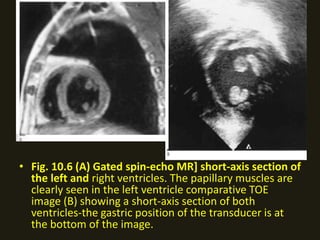

• Fig. 10.6 (A) Gated spin-echo MR] short-axis section of

the left and right ventricles. The papillary muscles are

clearly seen in the left ventricle comparative TOE

image (B) showing a short-axis section of both

ventricles-the gastric position of the transducer is at

the bottom of the image.